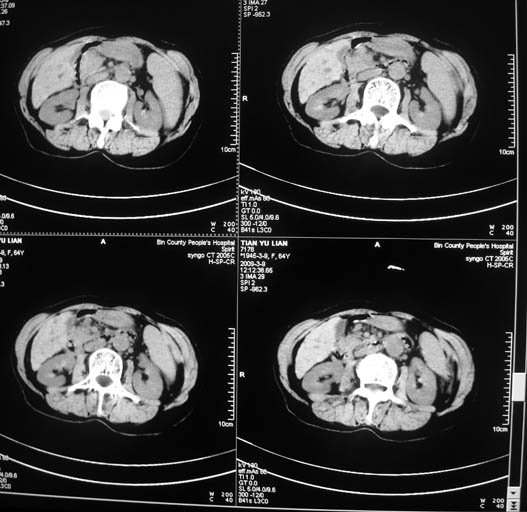

标题: CT18578:女,64岁,腹痛。 [打印本页]

标题: CT18578:女,64岁,腹痛。

女,64岁,腹痛。彩超示肝占位。

肝硬化肝癌,瘤栓?肝总管扩张。

1)肝右叶占位性病变,性质待定(不排除巨块型肝癌可能);建议行进一步检查。2)胆囊炎。3)脾大。

肝右叶占位性病变,考虑型肝癌可能!

1.肝脏形态不太规整,肝内胆管扩张,考虑有肝硬化,建议问病史。

2.肝右叶占位性病变,肝癌可能性大。

3.脾脏增大。

肝硬化肝癌,门脉右支瘤栓肝总管扩张